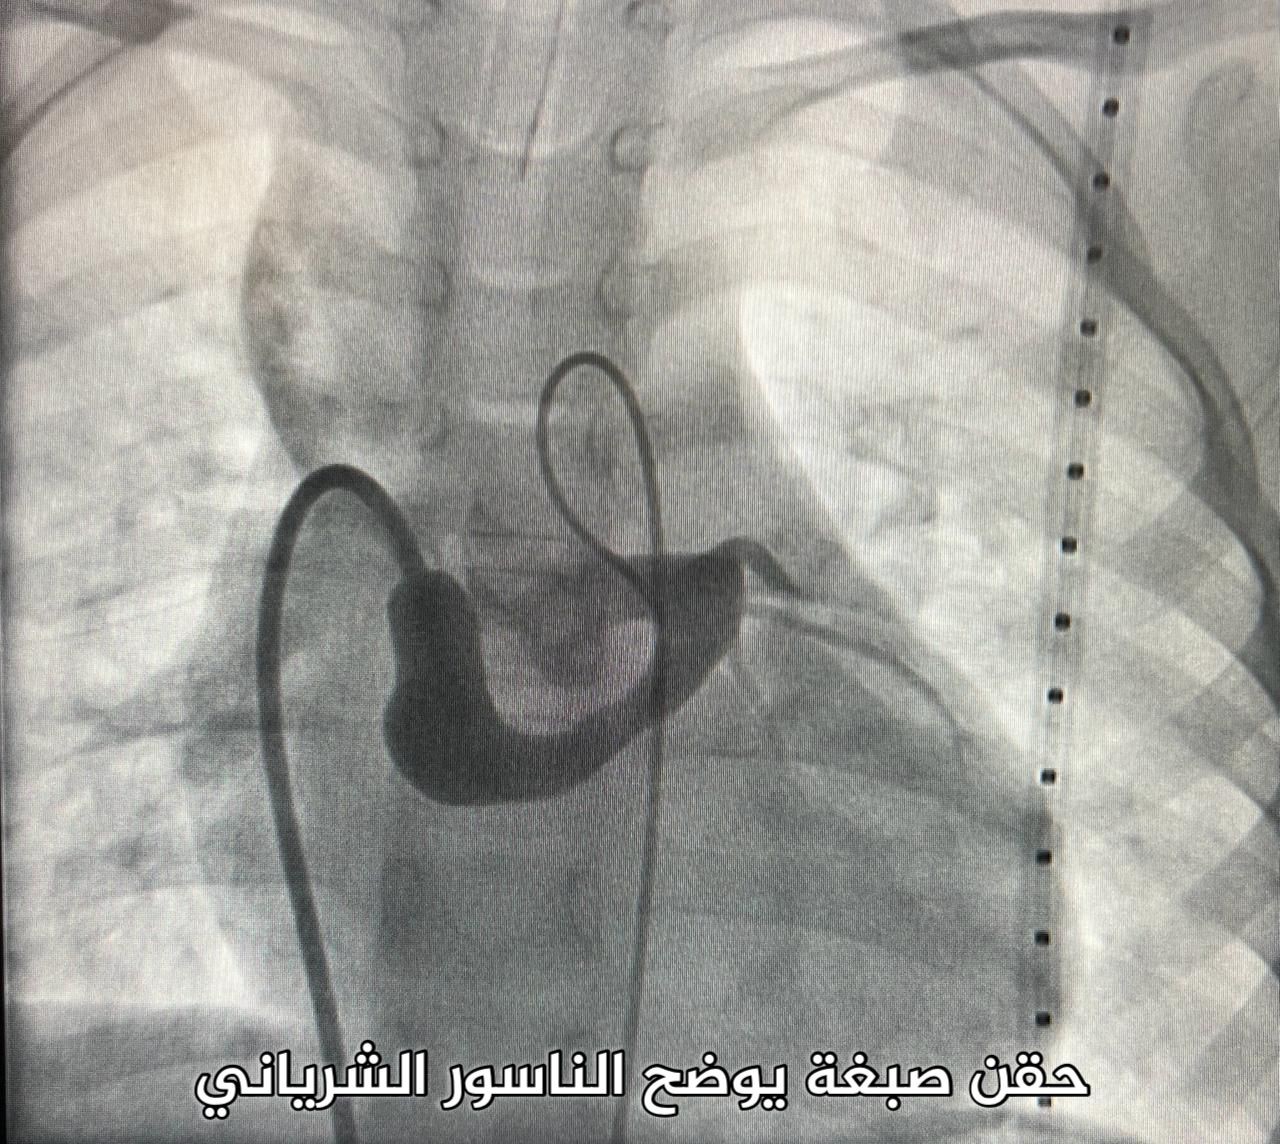

وأوضح التجمع أن الفحوصات والتحاليل الطبية التي أُجريت للطفل بينت وجود الناسور في المنطقة الكامنة بين الشريان التاجي الأيسر والأذين الأيمن مما استدعى الفريق المعالج في قسم الأطفال بالمركز للقيام بتدخل طبي عاجل.

وأشار إلى أنه تم إغلاق الناسور الشرياني لمنع حدوث الجلطات الشريانية وفشل عضلة القلب والالتهاب لا سمح الله، حيث تكللت العملية بالنجاح ولله الحمد في فترة زمنية لم تزد عن ساعة واحدة من خلال إجراء القسطرة الشريانية، وبعد الاطمئنان على الحالة الصحية للطفل غادر المركز مع أسرته مصحوبا بالسلامة والعافية.